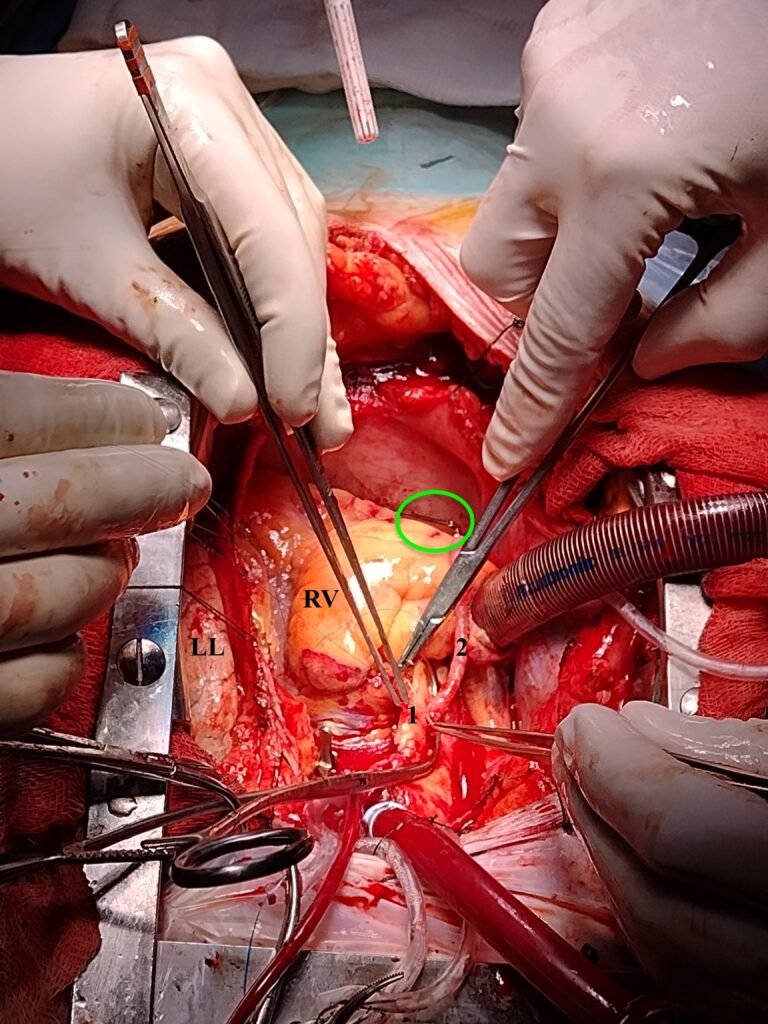

Proximales en la aorta ascendente. Un clamp lateral ocluye en forma parcial la aorta ascendente. Se observa claramente la cánula aórtica (roja) y la venosa (más oscura) en la aorta ascendente y el atrio derecho. El clamp parcial así colocado sirve para realizar una anastomosis exangûe.

En (1) la anastomosis en sí. Ahora aumente y siga en (2) y el óvalo verde el trayecto del bypass que se dirige hacia la coronaria derecha en la cara inferior del corazón. El puente se halla perfectamente alineado y un clamp tipo bulldog (óvalo verde) lo ocluye temporariamente.